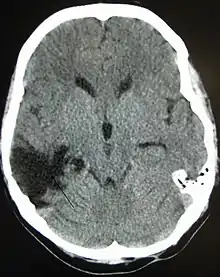

| CT scan showing cerebral contusions, hemorrhage within the hemispheres, and subdural hematoma. There is also displaced skull fracture of left transverse parietal and temporal bones.[2] | |

Hematomas, also focal lesions, are collections of blood in or around the brain that can result from hemorrhage.[11] Intracerebral hemorrhage, with bleeding in the brain tissue itself, is an intra-axial lesion. Extra-axial lesions include epidural hematoma, subdural hematoma, subarachnoid hemorrhage, and intraventricular hemorrhage.[38] Epidural hematoma involves bleeding into the area between the skull and the dura mater, the outermost of the three membranes surrounding the brain.[11] In subdural hematoma, bleeding occurs between the dura and the arachnoid mater.[23] Subarachnoid hemorrhage involves bleeding into the space between the arachnoid membrane and the pia mater.[23] Intraventricular hemorrhage occurs when there is bleeding in the ventricles.[38]

The preferred radiologic test in the emergency setting is computed tomography (CT): it is quick, accurate, and widely available.[79] Follow-up CT scans may be performed later to determine whether the injury has progressed.[10]